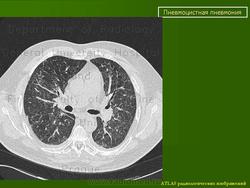

Рентгенологическая картина ПП

На рентгенограмме грудной клетки, как правило, выявляются двусторонние симметричные интерстициальные инфильтраты, однако в 20% случаев патологические изменения отсутствуют (Am J Roentgenol 1997; 169: 967). В прикорневых отделах легких определяется облаковидное понижение прозрачности, мелкоочаговые тени, располагающиеся симметрично в обоих легочных полях в виде крыльев бабочки. Такие изменения получили название облаковидных, пушистых инфильтратов, создающих вид «ватного» легкого. В ряде случаев встречаются атипичные рентгенологические признаки (инфильтраты периферической или латеральной локализации, лобарные или сегментарные, инфильтраты, располагающиеся в верхних отделах легких, как при туберкулезе, единичные в виде узлов). Довольно часто развивается пневмоторакс, который является характерным осложнением этого заболевания [1, 5-8]. На рис. 1, 2 приведены рентгенологические изменения легких у больных ПП.

Использование метода КТ позволяет обнаружить диффузные изменения в легочной ткани. Отсутствие патологических изменений на снимках, полученных методом КТ с использованием тонких срезов, не является основанием для исключения ПП [1, 5-8].

Выделяют острую и фиброзирующую форму пневмоцистной пневмонии по КТ + варианты на их фоне.

(Спиральная и многослойная компьютерная томография : учебн. пособие : в 2 т. /Матиас Прокоп, Михаэль Галански ; пер. с англ. ; под общ. ред. А.В.Зубарева,Ш.Ш.Шотемора. – 3е изд. – М. : МЕД прессин форм, 2011.)